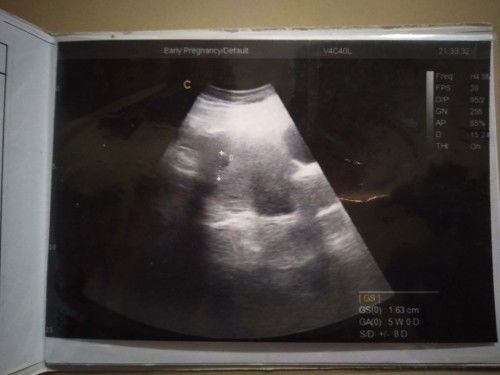

Hpht 11 Juli, USG pertama tgl 22 Agustus belum terlihat kantung janin. USG ke 2 13 September dengan dokter yg berbeda. . Hasil #seriusnanya #bantusharing UK 5week ada kantung janin . Normal kah?